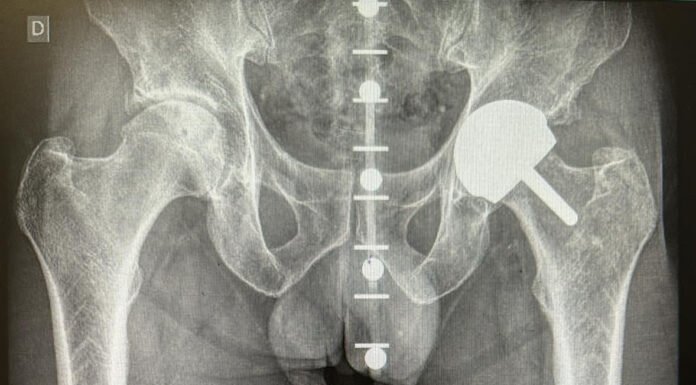

El servicio de Traumatología y Cirugía Ortopédica del Hospital Quirónsalud Sagrado Corazón ha incorporado un software de reconstrucción tridimensional para la colocación más precisa de prótesis de cadera....